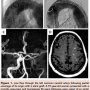

Antegrade cerebral protection strategies after the construction of the distal anastomosis and the use of retrograde cerebral perfusion might lower the risk of stroke in patients that need circulatory arrest (Figure 2).22-25 Careful preoperative evaluation of patients with multidetector CT and aortic echocardiography allows operative planning and can guide aortic clamping and cannulation strategies. The benefits of retrograde cerebral circulation are primarily two-fold. First, there is homogeneous cooling of the brain. Second, it flushes embolic debris from the cerebral vasculature.26 Effective nutrient delivery is best achieved with antegrade cerebral protection.26 Most surgeons resume antegrade cerebral and systemic circulation after the construction of the distal aortic anastomosis. This is usually performed by placing the aortic cannula in a side arm of the aortic interposition graft. This is in preference to retrograde systemic circulation (via femoral vessels) after a period of circulatory arrest and avoids embolization of distal aortic debris.